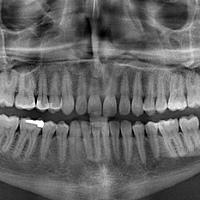

• Panoramisch: Zeigt die Sicht auf die Zähne, den Nasenbereich, die Nebenhöhlen und die Kiefergelenke. Wird normalerweise angefertigt, wenn eine kieferorthopädische Behandlung nötig ist.